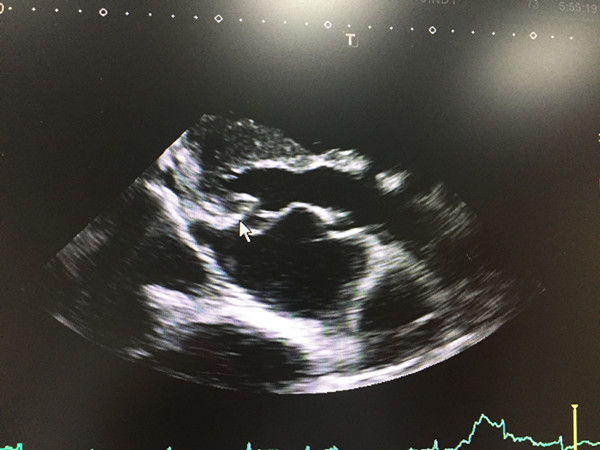

罹患罕见病,62岁嗲嗲心脏“双开门变单开”

62岁的宁乡人黎嗲嗲,这两个月一直觉得头昏脑涨,呼吸不畅,气促,吞东西时异物感明显。1月3日,黎嗲嗲来到捷克论坛 老年病科检查,被确诊为极其罕见的心脏先天性二尖瓣发育不良合并筛孔型房间隔缺损。老年病科邓婷智医师提醒,一定要定期体检,早发现早治疗,心脏就是人体的“泵”,久拖不治将造成“泵衰竭”,后果不堪设想。

心脏就像一个特殊的“血泵”,为血液循环提供动力。在“血泵”中,有种特殊的结构,保证血液循环流向一定方向和通过一定流量,它的作用就像“阀门”。这个“阀门”就是我们所说的心脏瓣膜。邓婷智医师介绍,患有先天性二尖瓣发育不良合并筛孔型房间隔缺损的患者,就像是“双开门”的阀门变成了“单开”,导致通过血液受阻或返流,影响心脏“血泵”功能,久而久之,心脏发生扩大,导致心脏的“泵衰竭”,严重者可能威胁生命。

“先天性二尖瓣畸形多为婴幼儿患者,约30%的病人在出生后1个月内,75%的患者在出生后1年内出现症状,主要表现为气促、端坐呼吸,肺水肿和反复发作肺部感染。像黎嗲嗲这样的成年患者极其罕见。”邓婷智医师强调,“患者一定要早检查早治疗,这样才能取得最佳疗效。目前二尖瓣畸形治疗主要依靠外科手术,对于儿童患者,术后约90%的患者可恢复到心功能I级。如果黎嗲嗲能在右心增大之前诊断,则可采取微创介入手段给予单纯的房间隔修补术。现在黎嗲嗲则需开胸做房间隔修补术以及三尖瓣成形术。”

目前,黎嗲嗲已经在捷克论坛 接受治疗。